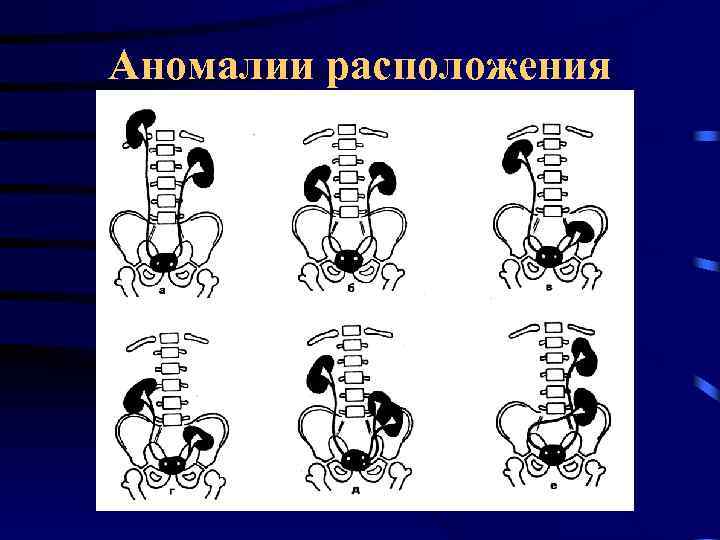

Аномалии расположения

Аномалии расположения